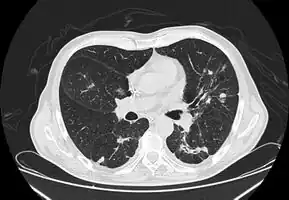

In the juvenile form, lung abnormalities are shown in high-resolution CT scans of the lungs, whereas in the chronic form plain X-rays may show interstitial and alveolar infiltrates in the central and lower lung fields.[14]

Imaging

Chest X-ray: Nodular shadows both lungs

CT chest: Paracoccidioidomycosis